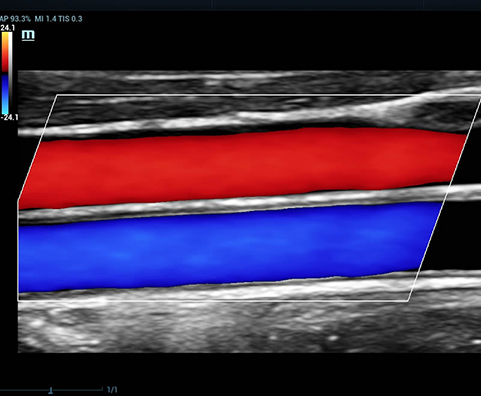

HR-flow™ - режим отображения кровотока с высоким временным и пространственным разрешением для точной и однородной визуализации сосудов, в том числе самых мелких

V-Mapping - оконтурирование с сенсорного экрана зоны интереса в протоколах сосудистых исследований

L11-3U – линейный датчик для исследований органов брюшной полости, скелетно-мышечной системы, поверхностных сосудов, а также в педиатрии. Поддерживает THI, Smart3D, iScape, биопсию, а также эластографию малых органов, V Flow периферийных сосудов и работает на всех режимах кроме CWD

LM16-4U – линейный датчик для исследований органов брюшной полости, скелетно-мышечной системы, поверхностных сосудов, а также в педиатрии. Поддерживает THI, Smart3D, iScape, биопсию, а также эластографию малых органов, V Flow периферийных сосудов и работает на всех режимах кроме CWD

Общая сонная артерия и яремная вена